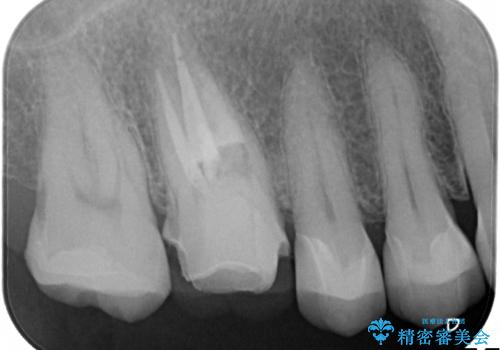

金属だらけの奥歯 根管治療のやり直しとセラミック化

- 神経のある歯を先にセラミック修復し、その後根管治療のやり直しを行う

→最終的にクラウンを製作し、きれいな奥歯を獲得する

神経の無い歯のクラウン(かぶせ物)は、根管治療を顕微鏡下でしっかりとやり直し、その後に土台の築造とかぶせ物の製作を行うことで今後問題が生じる可能性を可及的に低くできます。

かぶせ物の種類:Bellezza

詰め物の種類:e.max press In